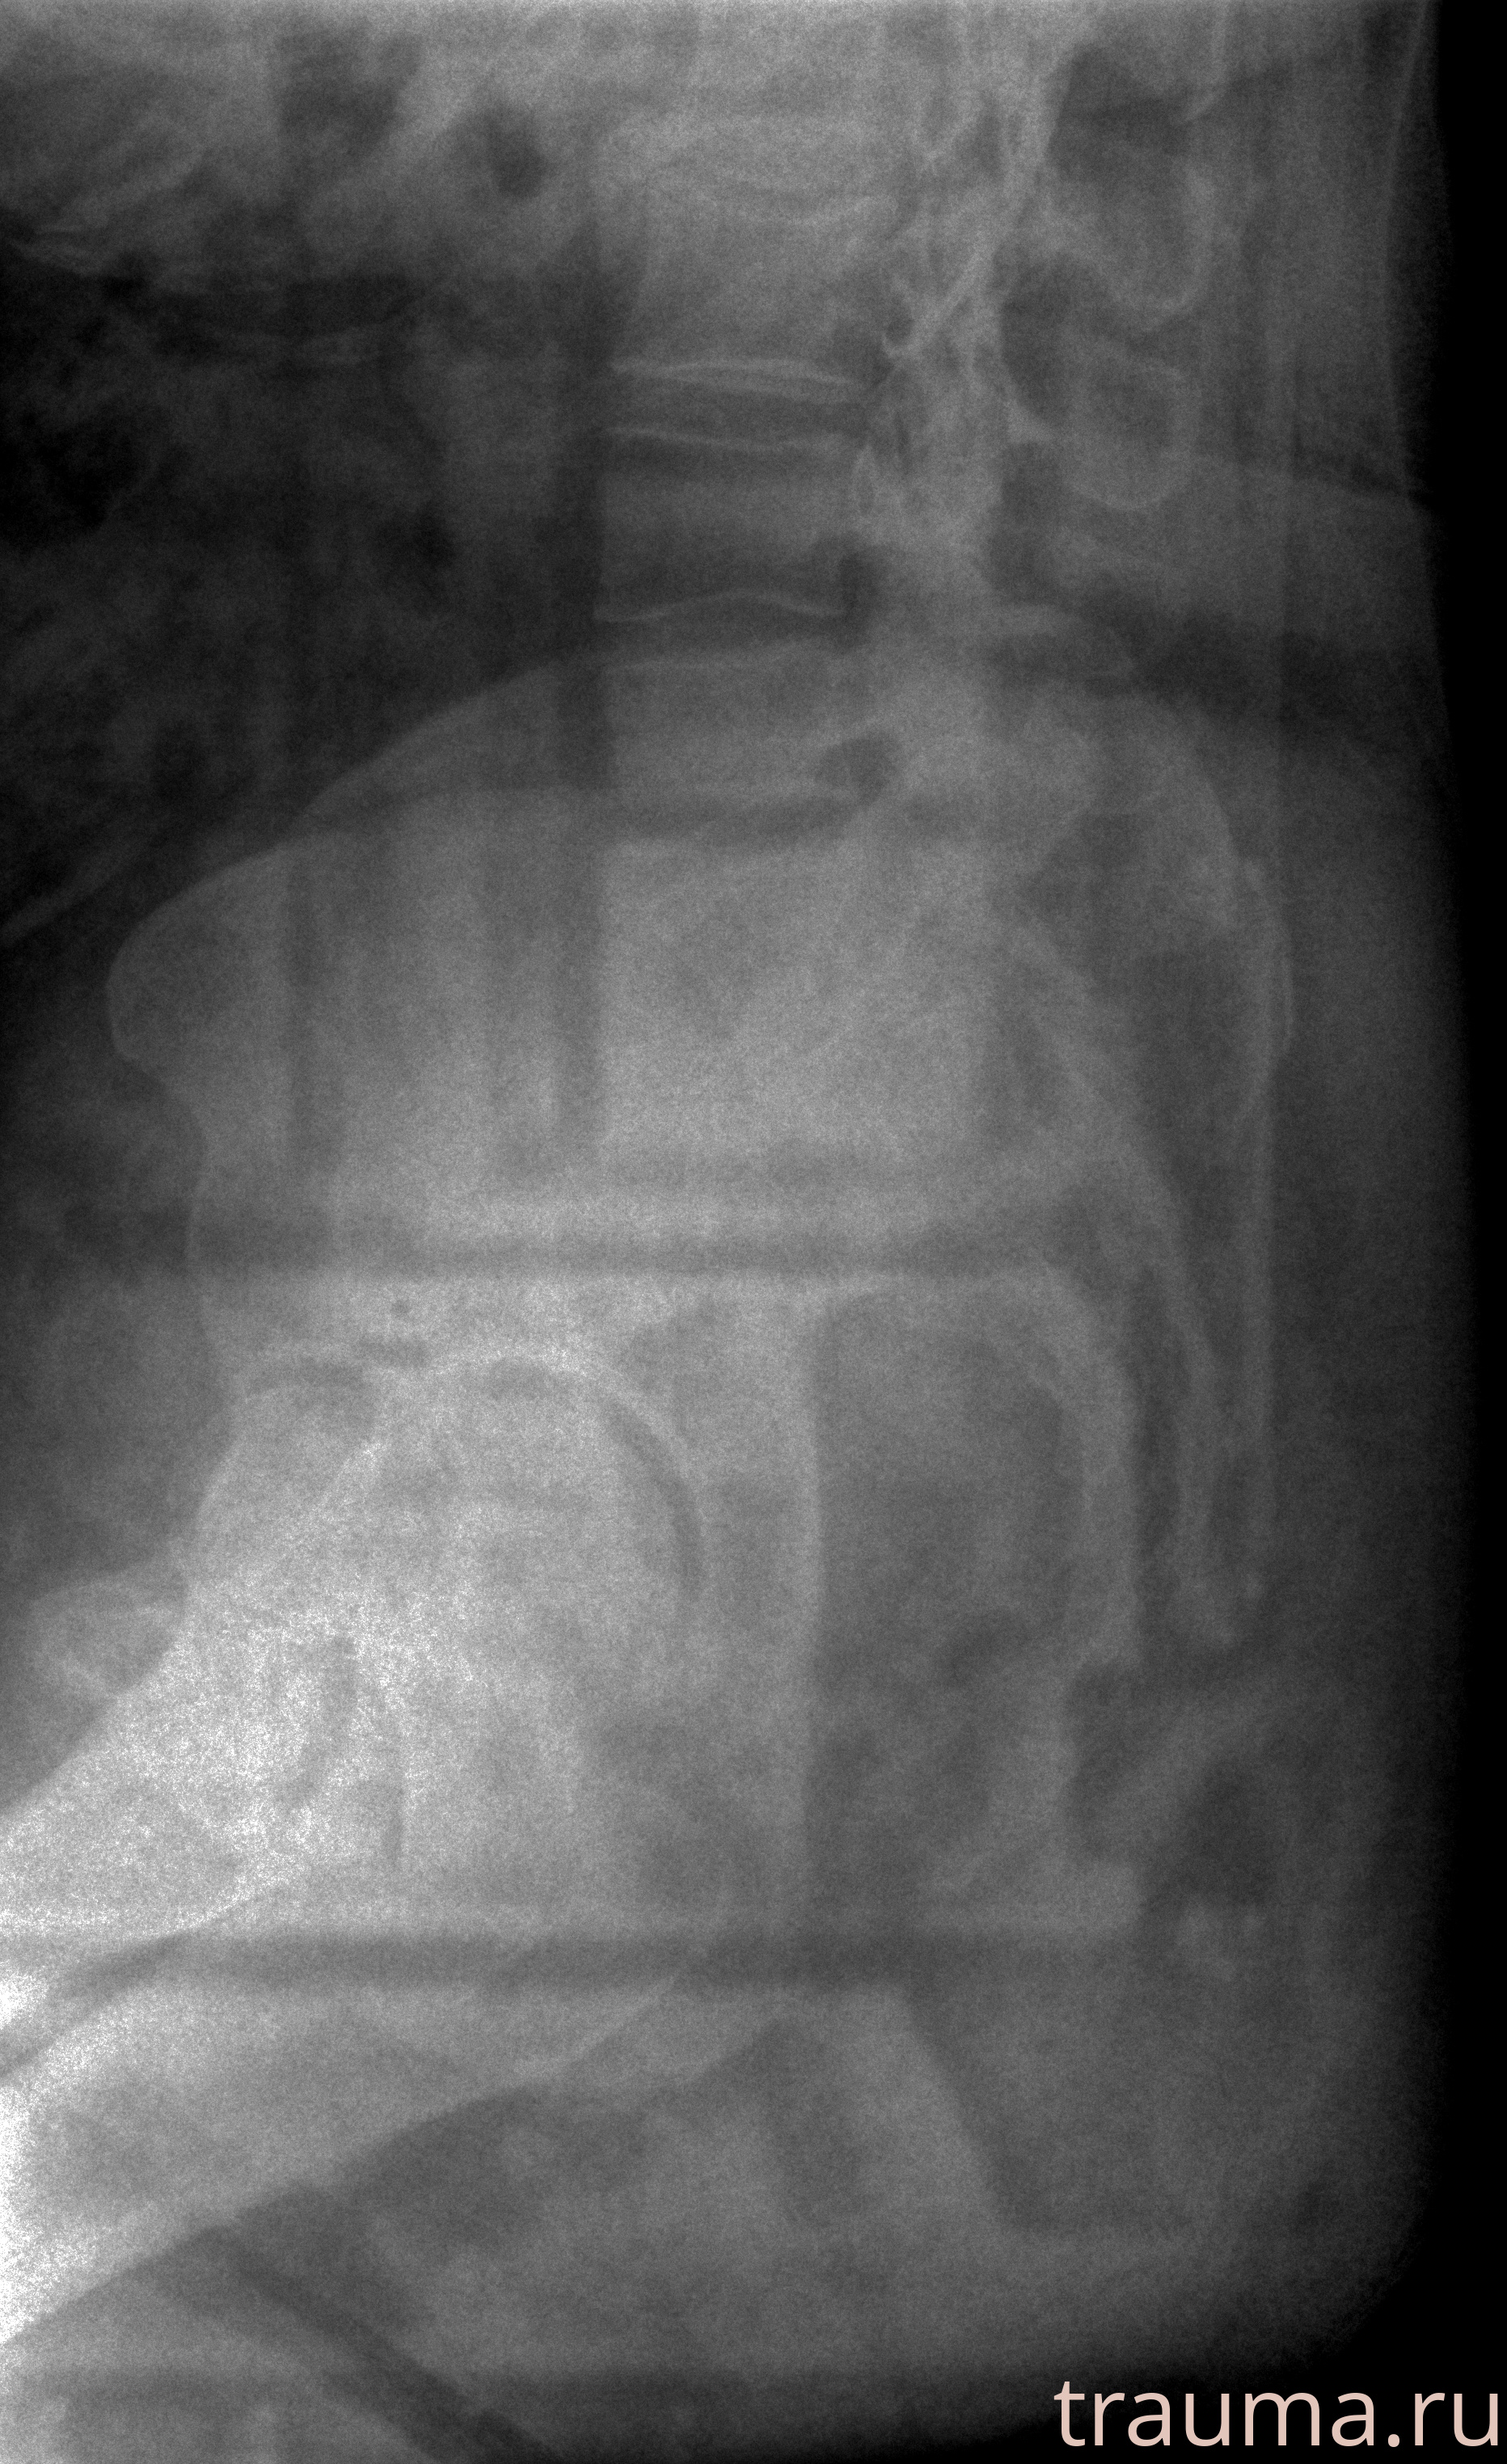

Рентгенограммы

Рентген на дому: по вашему адресу приезжает врач-рентгенолог, травматолог-ортопед с мобильным рентгеновским аппаратом, проводит диагностику травмы или заболевания, делает необходимые рентгенограммы, дает рекомендации по дальнейшему лечению. Получить качественные снимки в домашних условиях возможно благодаря уникальной методике, разработанной МосРентген Центром для института  Склифосовского